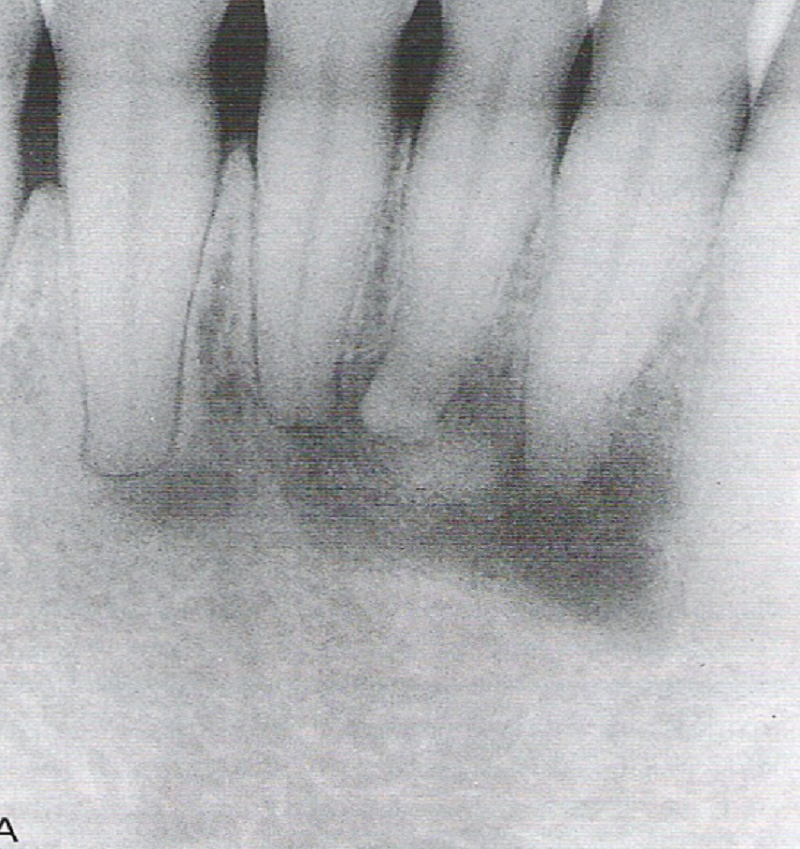

{"name":"Oral Path ID Chapter 6-9", "url":"https://www.quiz-maker.com/QPREVIEW","txt":"This condition is linked with Keratinosis of the palms of the hands & the soles of the feet. Individuals with this condition are likely to experience tooth mobility and premature tooth loss., This Term is used to describe The Appearance of type III (hypomaturation) Amelogenesis Imperfecta, Radiographs of a person with this condition appear to have a multilocular or “soap bubble” appearance","img":"https://www.quiz-maker.com/3012/CDN/92-4508546/final-pic-1.png?sz=1200"}